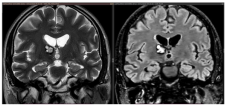

Figure 4.

Examples of deep-seated asymptomatic CMs. (a). Axial, sagittal, and coronal T1-weighted MRI with gadolinium and axial GRE T2*-weighted MRI of the left caudate nuclei CM. (b). Sagittal and axial T1-weighted MRI with gadolinium. (c). Coronal and axial GRE T2*-weighted MRI and (d). Axial T1 and GRE T2*-weighted MRI, showing a CM of the corpus callosum. (e). Coronal T2-weighted and FLAIR MRI. (f) Axial and sagittal FLAIR MRI and (g). Axial GRE T2* and T1-weighted MRI showing a right thalamic CM. Note the “blooming artifact” on axial GRE T2*-weighted MRI due to pools of deoxygenated blood and deposits of hemosiderin and calcium (yellow arrows) and the classic “popcorn” appearance on FLAIR-weighted MRI with mixed signal intensity, expression of various blood breakdown products (red asterisk) of the CMs.